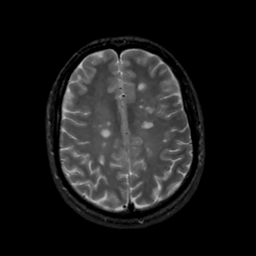

MR Study #16, June 23, 1991 -- Slice #35

[Home][Help][Clinical][Tour 1][Tour 2] Slice 35